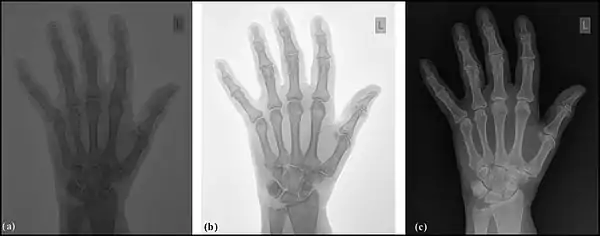

Examples of contrast enhancement applied to a radiograph of the wrist: (a) unprocessed image, (b) window and level adjusted and (c) an inverted grey scale.